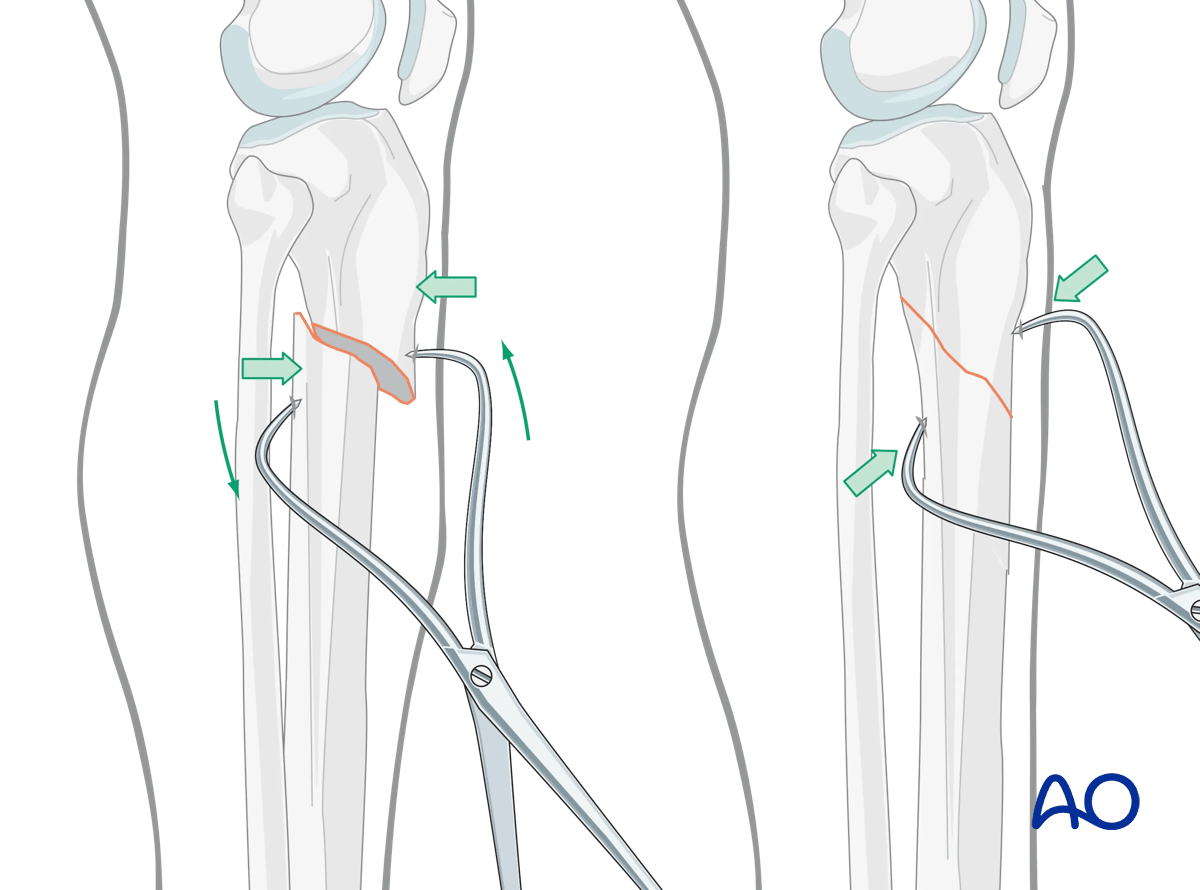

Oblique fractures

If the fracture is oblique, a bone clamp, placed percutaneously, with its tips perpendicular to the fracture plane, can be used to compress the fracture surfaces. Together with some traction, this helps restore length as well as fracture apposition.

Suprapatellar intramedullary nailing, reduction of oblique fractures